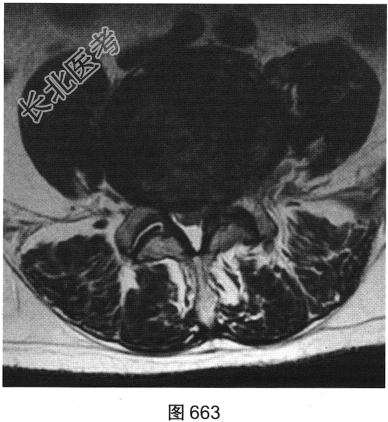

- 多项选择题3.[提示]患者行腰椎MRI检查,如图660~图663所示。患者MRI的T2压脂像上, 部分椎体上、下缘高信号提示( )

A、椎体感染所致的骨髓水肿

B、肿瘤侵蚀破坏

C、椎体轻度压缩骨折

D、脊椎结核

E、退变所致的终板炎

F、椎体脂肪化

- 多项选择题4.综合X线、CT和MRI图像,该患者有以下哪些腰椎退变征象( )

A、终板炎

B、腰椎间盘突出

C、许莫结节

D、黄韧带肥厚

E、腰椎管狭窄

F、腰椎间盘脱出,髓核游离